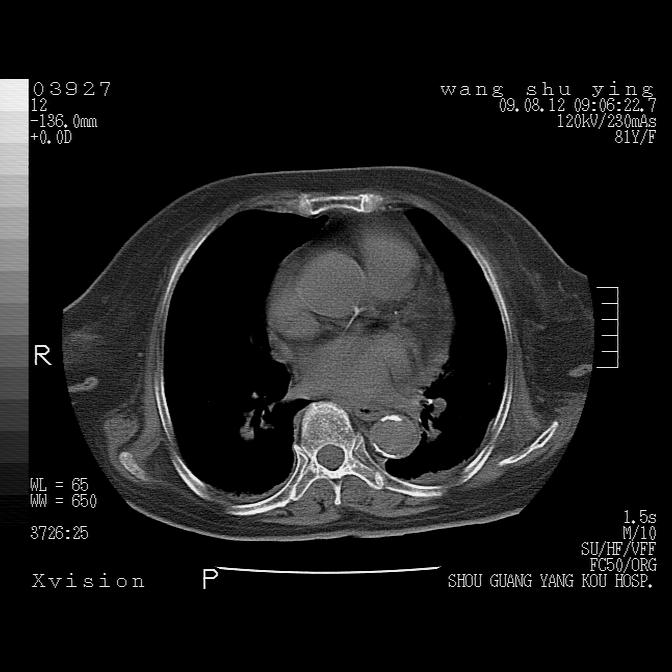

以下是引用帅河马在2009-8-12 12:59:00的发言:[br]两肺感染性病变伴双侧胸膜肥厚。[br]左侧甲状腺腺瘤不除外。[br]腹水+心包积液。[br][br][本贴已被 帅河马 于 2009-8-12 13:14:32 修改过]

以下是引用sdzyy在2009-8-12 18:17:00的发言:[br]两肺感染性病变伴双侧胸膜肥厚。[br]左侧甲状腺腺瘤不除外。[br]腹水+心包积液。[br]支持

以下是引用随光逐影在2009-8-12 19:42:00的发言:[br]1)两肺感染性病变伴双侧胸膜肥厚。2)不排除左侧甲状腺腺瘤。3)肝脏占位性病变;建议行进一步检查。